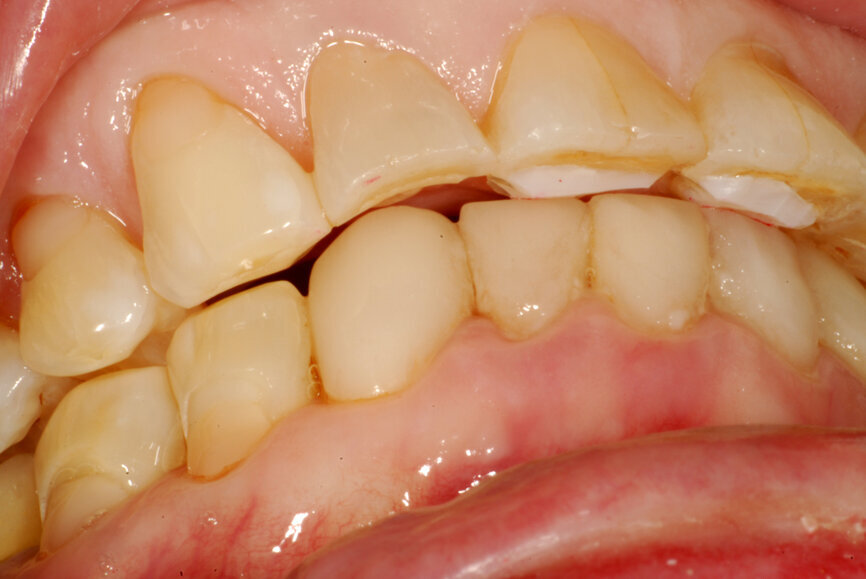

Fig. 15: Occlusion with the mandible in centric relation and a significant open bite.

Fig. 16: Occlusion with intercuspation but a non-functional

mandibular position.